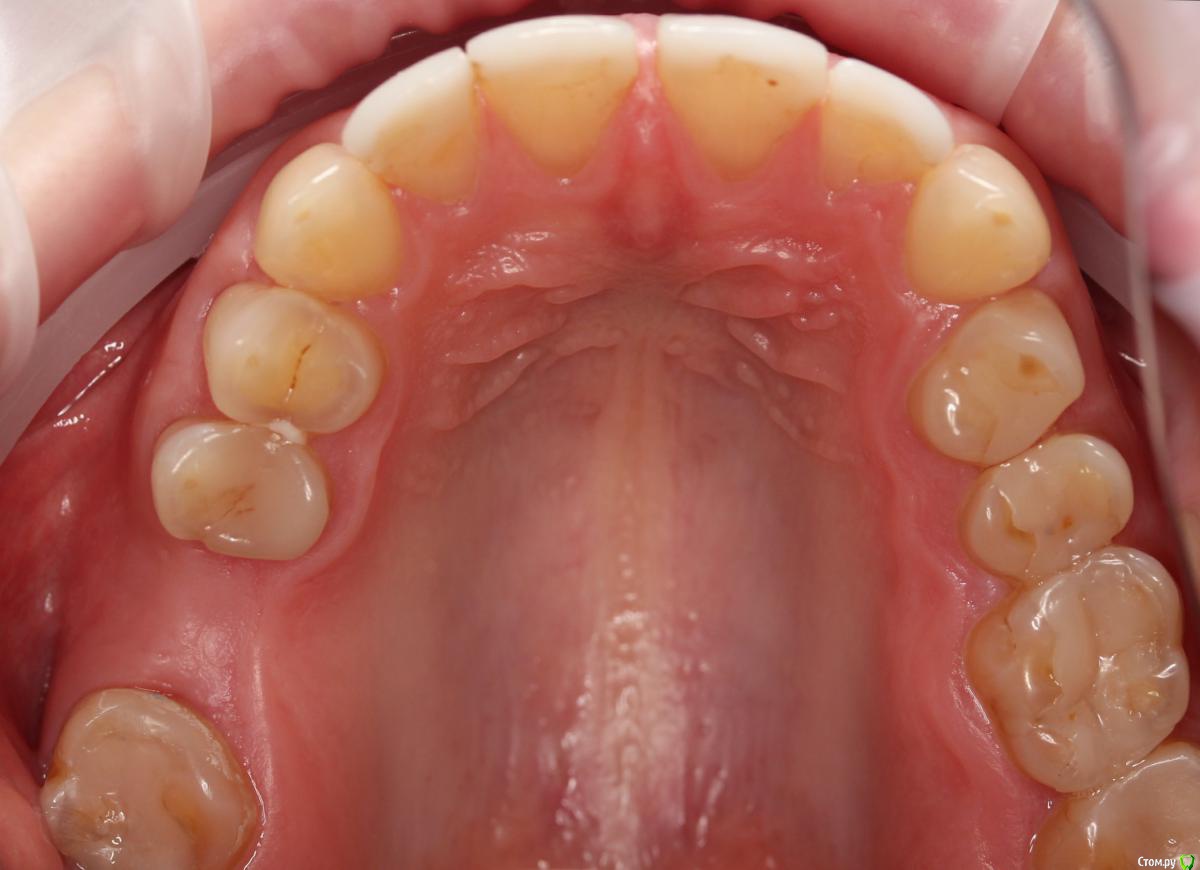

Dmitry DK Опубликовано 10 сентября, 2019 Поделиться Опубликовано 10 сентября, 2019 Фотопротокол к сожалению не полный, но ничего особенного и не проводилось. 1) Открытый синус, удален пломбировочный материал из пазухи, уложен 1 г Bio-oss 2) через 6 мес имплантация Straumann SP 4.1\10 Результат через год 9 Ссылка на комментарий